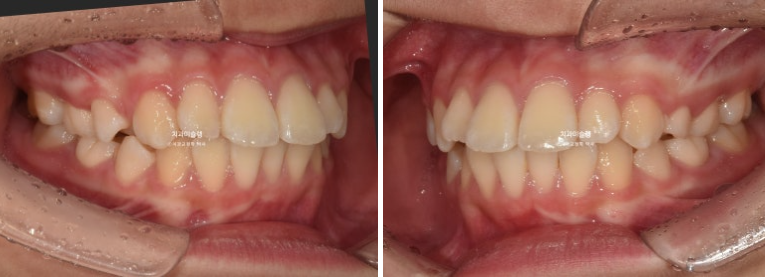

24.09

24년 9월까지 6개월간 첫세트 20개 장치를 모두 낀 후 모습입니다.

전반전이 끝났다고 표현할 수 있겠습니다.

내려와 있던 가운데 앞니 두 개는 위로 올라가면서 높낮이가 맞아졌고

앞니돌출은 개선이 되었습니다.

그 사이 남아있던 유치가 빠지고 영구치가 잘 나오고 있습니다.